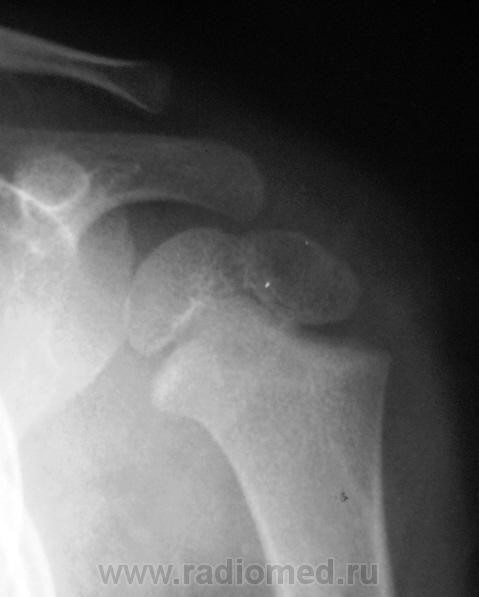

Перелом левой ключицы

Может быть, если есть клиника, но немного сомнительно. А почему опять нет второй проекции?